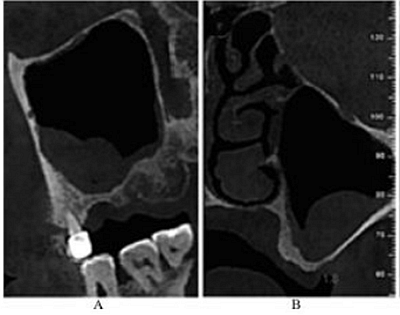

CBCT示:上頜竇內見液平面約達竇腔1/3(考慮為沖洗液未吸干凈),上頜竇垂直高度得到補足,26牙高度8.4mm,27牙高度為9.5mm(圖3)。患者拒絕穿刺液送病理檢查。

圖3 上頜竇外提升術后CBCT。

注:A,矢狀面;B,26頰舌向切面;C,27頰舌向切面;D,28頰舌向切面。